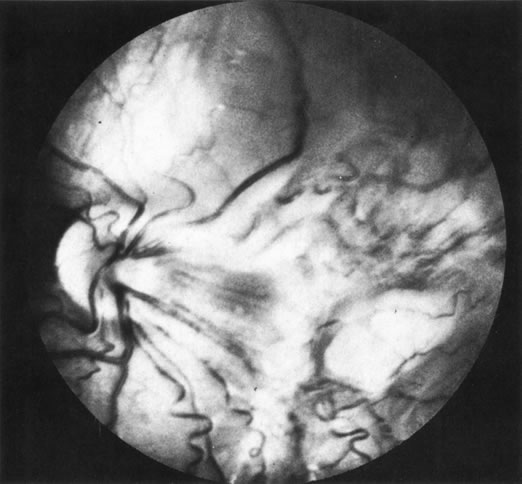

3. Diffuse retinoblastoma, which accounts for less than 2% of cases, often does not produce a discrete tumor (Fig. 26). The diffuse cases I have managed have had atypical retinal detachments without clinical, CT, or ultrasonographic evidence of a calcified tumor mass. Diagnosis has been established with an intraocular FNAB.55

Fig. 26. Diffuse retinoblastoma without an obvious tumor mass.